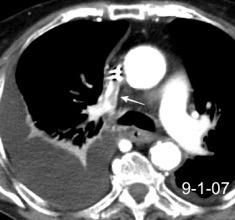

Síndrome de afectación postcardiaca (postcardiac injury)

Post infarto 1-7 % (Dressler)

Trauma cerrado Implantación marcapasos

Cirugía cardiaca. 17-31% (Post.pericardiotomía)

3707 pacientes 29 Derrames (0,78%) > de 25% del hemitórax

Todas menos 2 Izdos.

Angioplastia

By-pass coronario 21-10-03